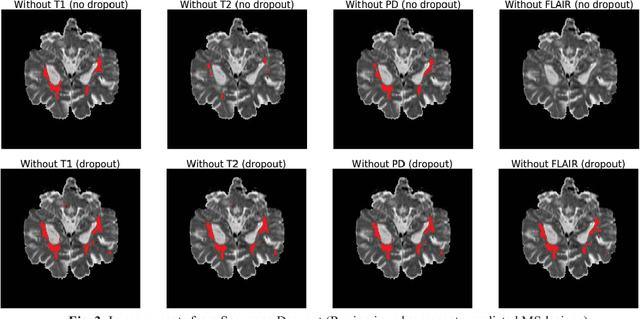

Abstract:Deep neural networks (DNN) have shown promises in the lesion segmentation of multiple sclerosis (MS) from multicontrast MRI including T1, T2, proton density (PD) and FLAIR sequences. However, one challenge in deploying such networks into clinical practice is the variability of imaging protocols, which often differ from the training dataset as certain MRI sequences may be unavailable or unusable. Therefore, trained networks need to adapt to practical situations when imaging protocols are different in deployment. In this paper, we propose a DNN-based MS lesion segmentation framework with a novel technique called sequence dropout which can adapt to various combinations of input MRI sequences during deployment and achieve the maximal possible performance from the given input. In addition, with this framework, we studied the quantitative impact of each MRI sequence on the MS lesion segmentation task without training separate networks. Experiments were performed using the IEEE ISBI 2015 Longitudinal MS Lesion Challenge dataset and our method is currently ranked 2nd with a Dice similarity coefficient of 0.684. Furthermore, we showed our network achieved the maximal possible performance when one sequence is unavailable during deployment by comparing with separate networks trained on the corresponding input MRI sequences. In particular, we discovered T1 and PD have minor impact on segmentation performance while FLAIR is the predominant sequence. Experiments with multiple missing sequences were also performed and showed the robustness of our network.